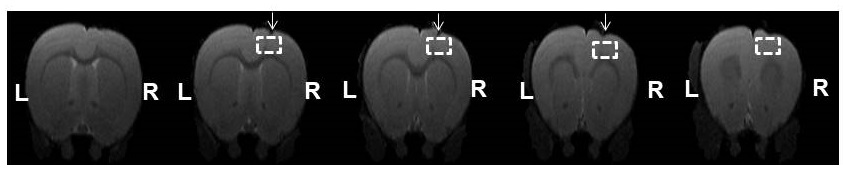

AAV8-hSyn-hM3D(Gq) expression in M1 was demonstrated using Cfos immunohistochemistry (Fig. 1).Viral injections in M1 demonstrated no major susceptibility artefacts as depicted on structural images of the rat brain (Fig 2). RsfMRI results were CNO dose-independent. Fig.3A and 3B compare ICA components obtained at baseline and post CNO respectively in a representative rat. The number of bilateral components post-CNO injection increased compared to baseline (6 versus 2). Fig.3.C and 3.D show the respective correlation matrices demonstrating a change in functional connectivity (fNC) for this rat upon CNO injection. The group fNC correlation matrices (3 rats, Fig.4.A and 4.B) evaluated at baseline and post-CNO confirmed a change in functional connectivity upon CNO injection. The baseline (Fig 4.C) and post-CNO connectograms (Fig 4.D) indicate increased fNC upon CNO activation in line with previous studies (5) with particularly enhanced motor cortical fNC.

Figure 2: Structural T2 RARE images indicating implantation of the AAV8-hSyn-hM3D(Gq) virus in the motor cortex of the rat (White voxel and arrow). Little susceptibility artefacts were detected. L: Left; R: Right